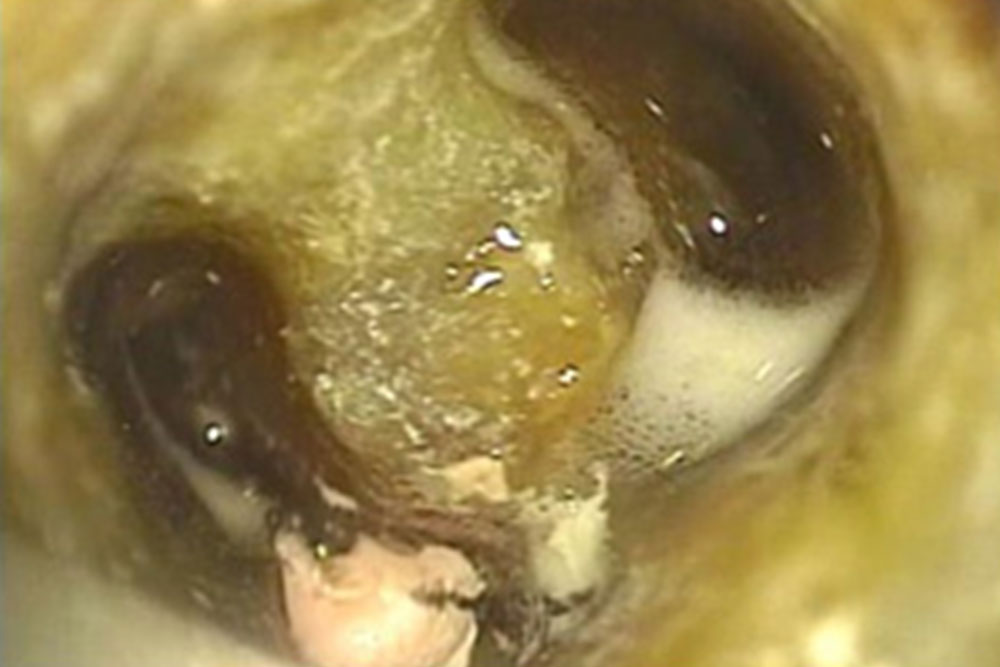

マイクロスコープを用いた精密根管治療の実施

マイクロスコープで視野を拡大して虫歯部分をすべて取った後、根の消毒を始めます。今回の歯は術前にCTで根の入り口が3つあることがわかっています。

根管内の消毒

根管充填

根の中の消毒が終わったら、最終的な薬を詰めて根の中の空洞を封鎖する根管充填(こんかんじゅうてん)を実施。

レジンという歯の治療に用いるプラスチックの材料を、当該歯に流し込み特殊な光を当てて固めます。(マイクロスコープの強力なライトでも固まってしまうので遮光のため、視界が黄色くなっています。)

歯の表面をよく乾燥させ、接着のために歯の表面を薬品で処理します。ここでも呼気や唾液による接着不良を防止するため、ラバーダム防湿(ゴム製のシートで歯を口腔内から隔離)をしています。